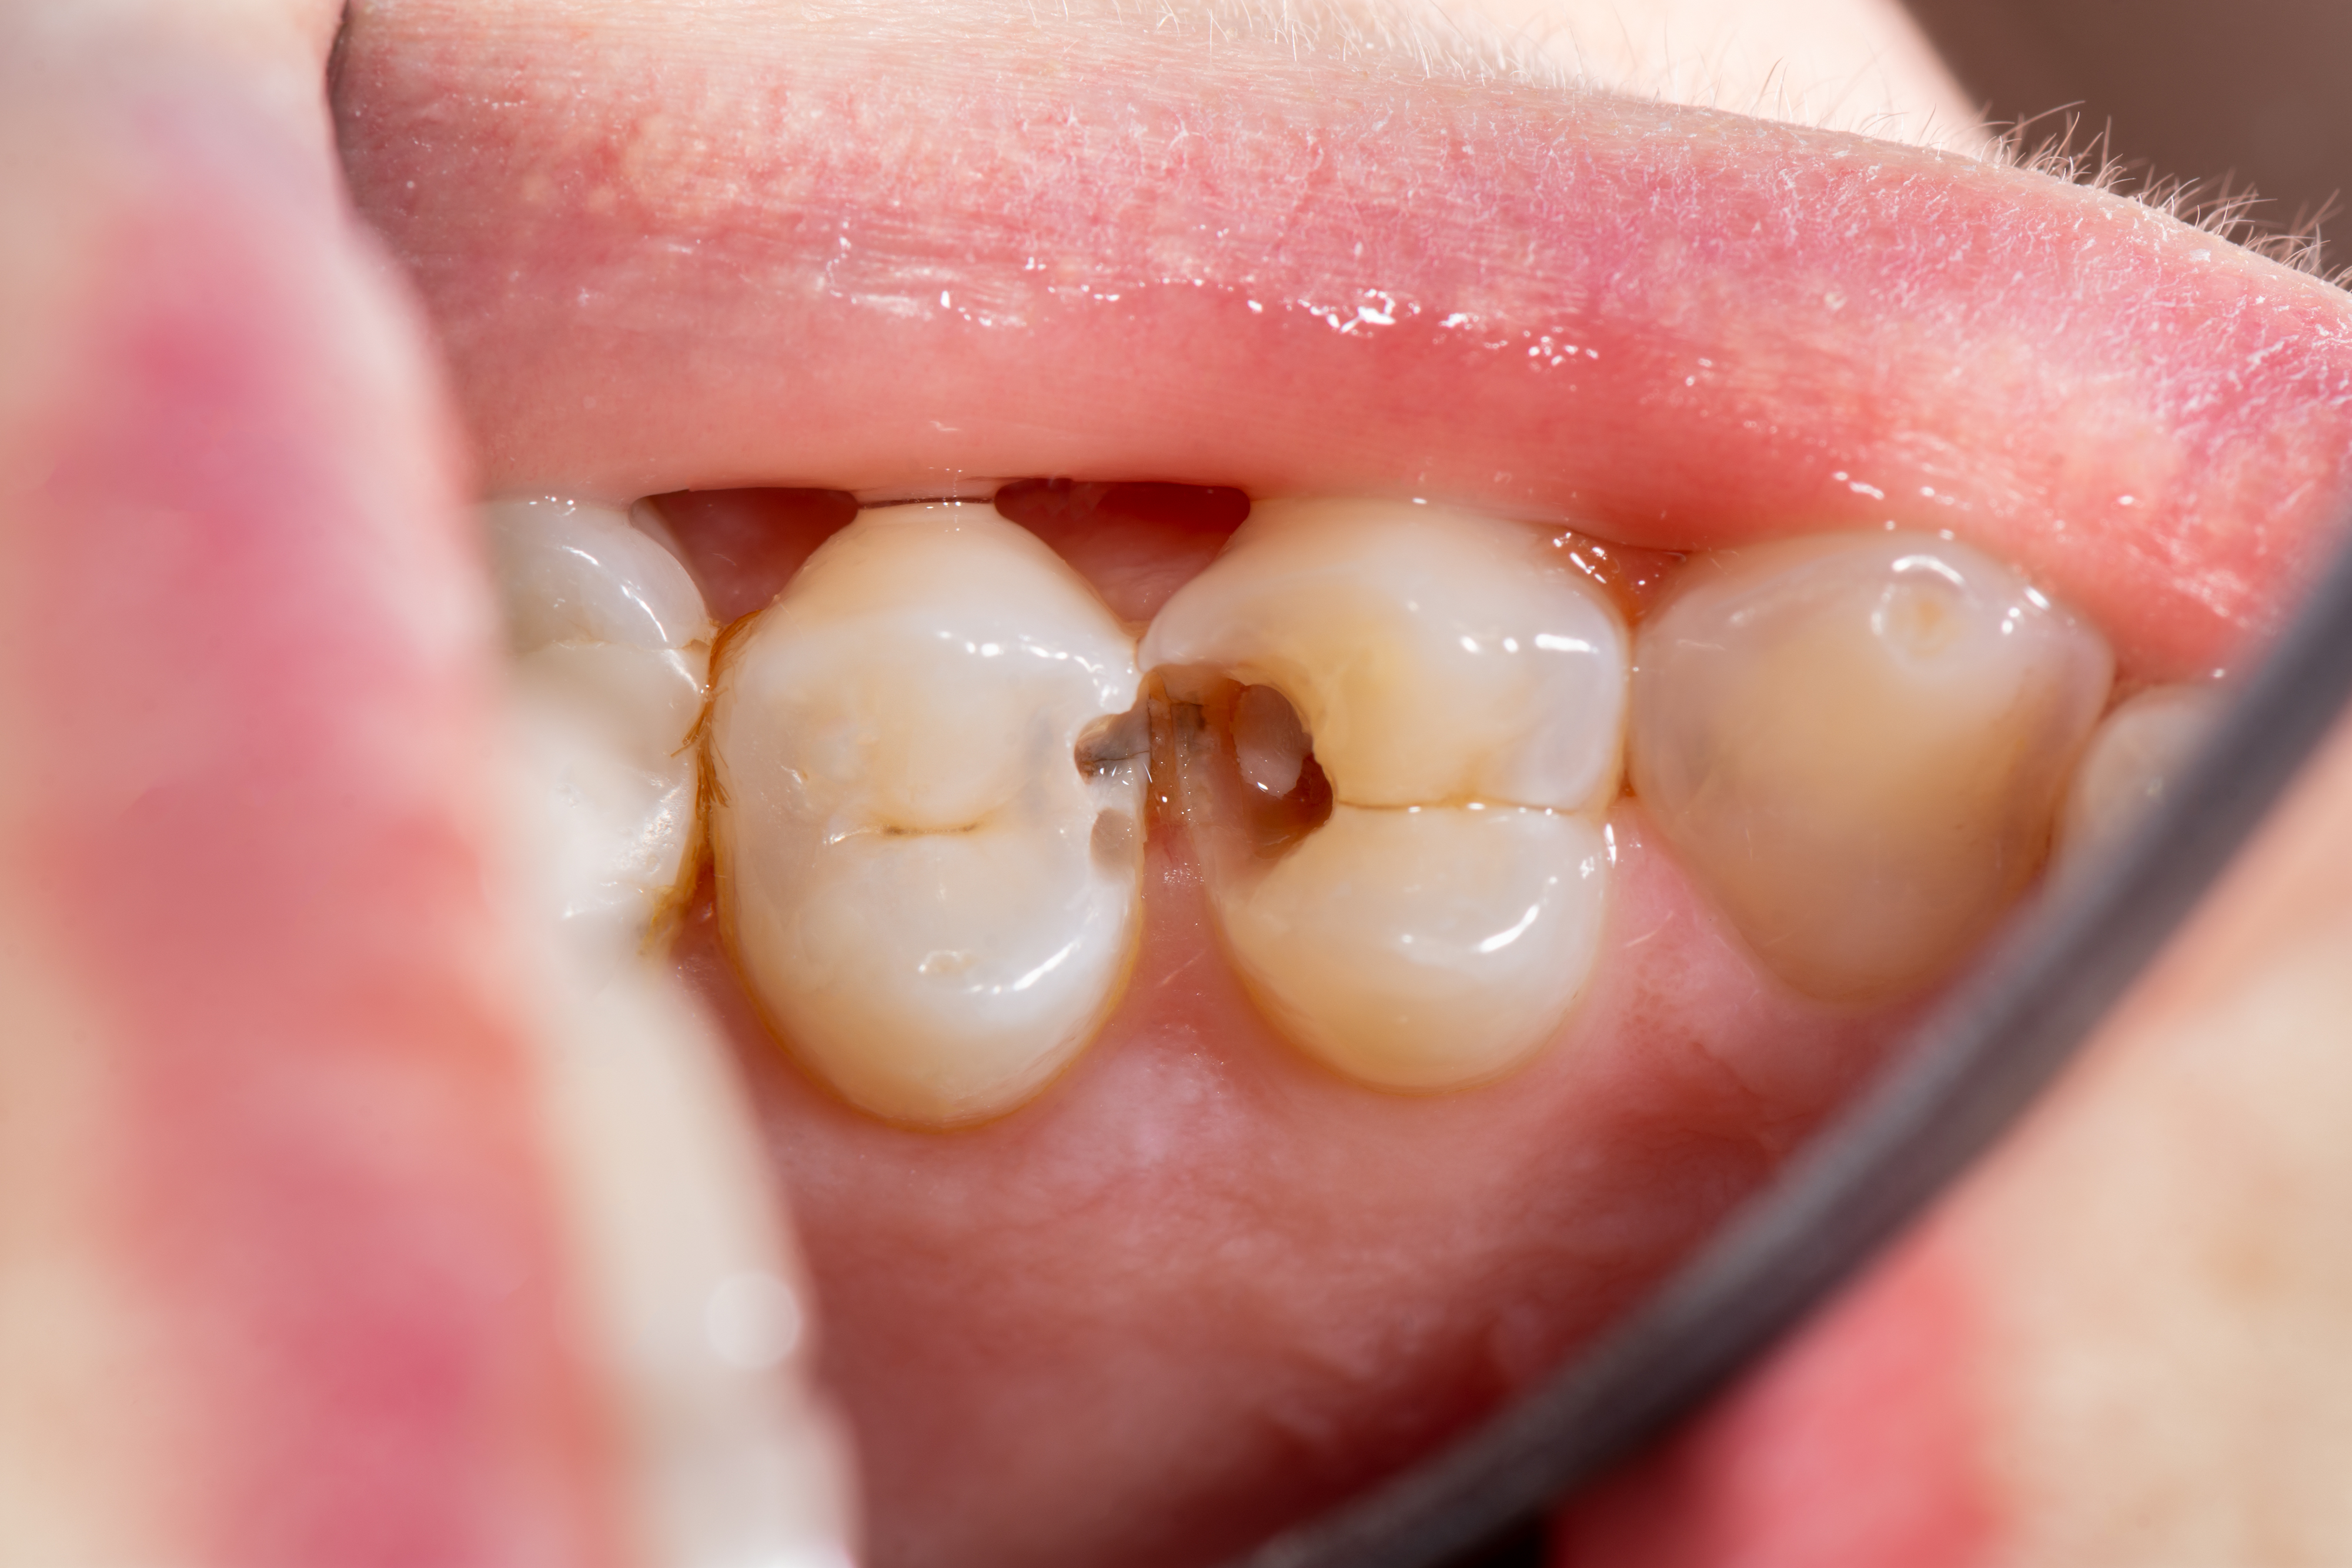

港人另一大牙齒問題即是齲齒,俗稱蛀牙。對於蛀牙問題,同樣預防勝於治療。

嚴重蛀牙的治療方式通常是杜牙根(根管治療),即在牙齒表面鑽洞入到牙的神經,用機械將神經中的血管、淋巴全部清除,替它消毒,再用不會產生化學作用的物質將其封住,令牙齒不再痛,接着做一個牙冠保護住它,牙齒又可以保留一段時間。但比起大費周章的治療,更重要的還是日常的預防。